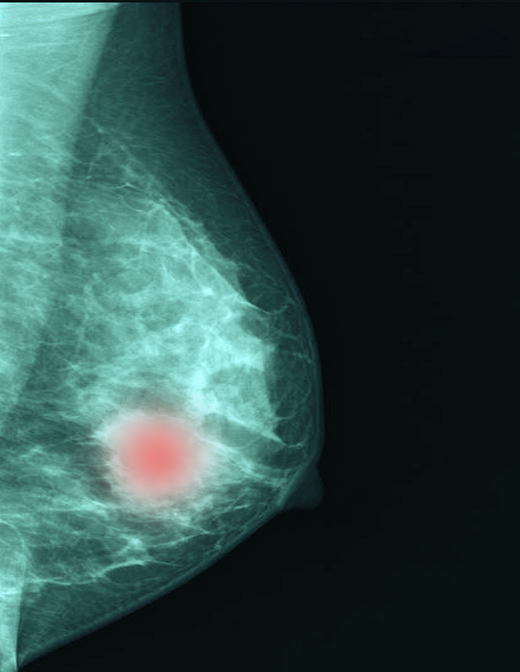

유방암이 간(肝)으로 전이되는 '유방암 간 전이' 과정의 새로운 메커니즘을 규명한 연구 결과가 국내에서 나왔다.

유방암은 2023년 세계 여성암 발생률 1위, 사망률 2위로 무서운 질환이다. 유방암으로 인한 사망률은 대부분 유방암 환자의 원격 전이(원발 부위의 암보다는 폐·간·뼈 등 다른 장기로 전이된 경우)로 인해 발생한다.